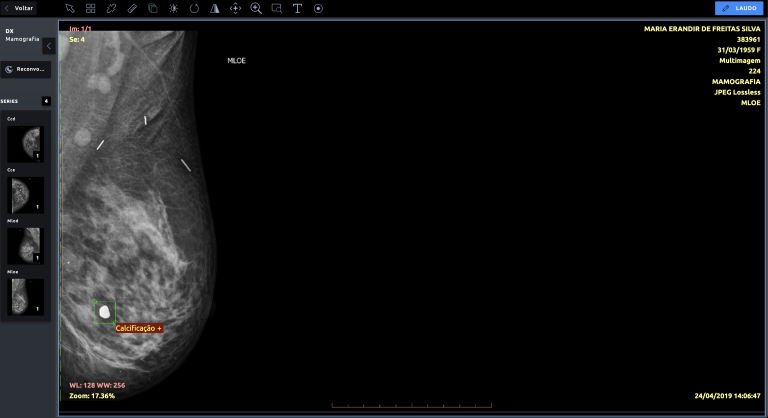

O Cofundador da startup afirma que, nos próximos anos, será fundamental o uso da inteligência artificial para processar as informações médicas, como é o caso dos exames por imagem. Uma das grandes vantagens do uso da IA é o uso de algoritmos que apoiam os médicos radiologistas na análise dos exames conforme a criticidade dos resultados. Dessa forma, exames mais graves serão priorizados e analisados com maior rapidez, acelerando e aumentando a assertividade dos tratamentos de forma eficiente.

Para André Castilla, Médico Radiologista e Cofundador da NeuralMed, soluções de inteligência artificial ajudam o setor a dinamizar o atendimento e diminuir o tempo para descoberta de patologias. “Nós vemos a DGS como um parceiro estratégico, que junto conosco vai trazer uma nova realidade para o setor da saúde, com dinamismo e otimização em laudos e diagnósticos”, acredita.